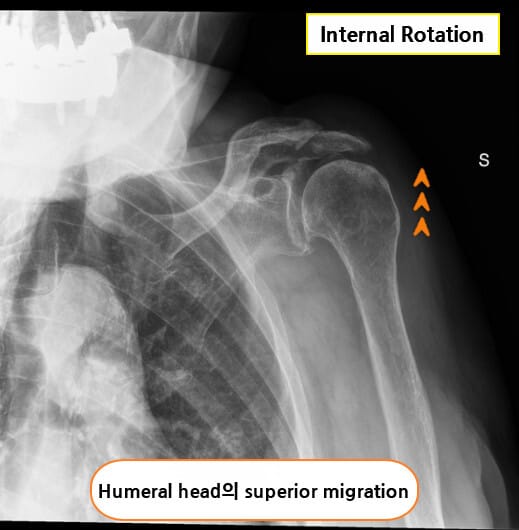

X-ray

회전근개 자체는 관찰되지 않지만, 상완골의 상방 전위(superior migration of humeral head), 견봉하 공간 협소(subacromial space narrowing), 석회화(calcium deposit) 등이 간접적으로 파열을 시사할 수 있습니다.